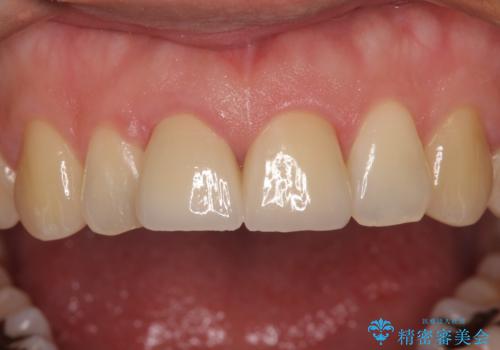

転んで欠けてしまった前歯 抜歯を回避してオールセラミッククラウンで審美回復

- 転倒により前歯を折ってしまったとのことで来院された患者様です。

右側の前歯は歯茎の中にまで及ぶ深い破折線があり、神経組織は既に失活していました。

左側の前歯は大きく歯冠が欠けてはいましたが、神経の生活反応が認められました。

強い衝撃を受けた歯であるため、定期的にレントゲン撮影を行い、歯根吸収が起きていたり、神経が失活していたりしないか確認を行い、ある程度安定したところでオールセラミッククラウンにて補綴治療を行うこととしました。